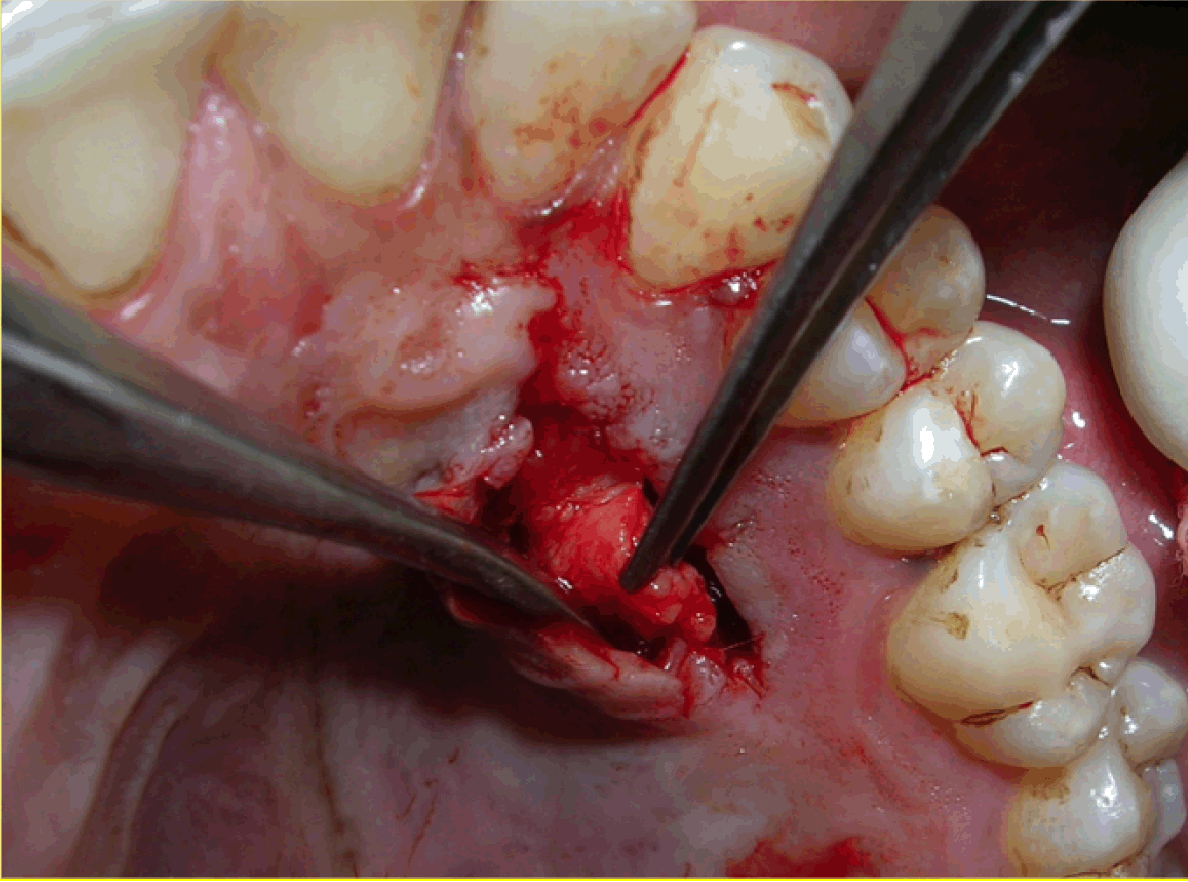

Case 1: A 36-year-old female reported with the chief complaint of sensitivity in lower right posterior teeth. On examination there was Millers Class III recession in relation to 44 and 45 (Figure 1). The width of attached gingiva was found to be inadequate since the tension test was positive. After phase I therapy, a pouch and tunnel technique utilizing a connective tissue graft was planned for root coverage. A sulcular incision was made through each recession area and the tissues gradually undermined including the base of the interdental papilla without the tip and the undermining extended up to the mucogingival junction so as to relax the flap sufficiently to allow placement of the connective tissue graft. Thus gradually a pouch and tunnel was prepared connecting the recipient sites for placement of the graft (Figure 2). The connective tissue graft was harvested from the palate using Liu's Class 1a incision (Figure 3). This graft was then placed using a technique described by Zabaluigi et al. where two resorbable sutures of different colors were placed, one on either side of the graft. Using these sutures, the graft was gradually manipulated into the pouch and through the tunnel to cover the adjacent recipient sites. Once the graft was completely inside the tunnel, it was positioned coronal to the cemento-enamel junction. The ends were sutured with a simple square knot (Figure 4). A periodontal pack was placed both at the recipient site as well as the donor site using an acrylic stent for the palatal placement.

Figure 3: The connective tissue graft was harvested from the palate using Liu's Class 1a incision.